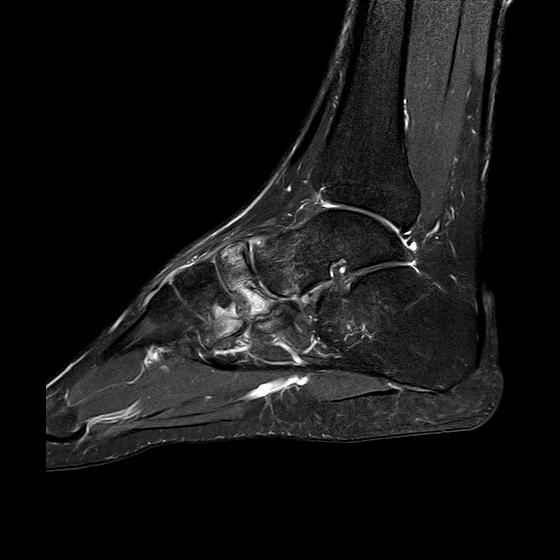

Дорогие коллеги, Мужчина 36 лет, пострадал около 8 месяцев назад в ДТП (водитель мотоцикла).

Подтаранный вывих лечили гипсовой лонгетой. Недиагностированным остался перелом ладьевидной кости, который беспокоит в настоящее время. Аваскулярный некроз кости, похоже. Добавил наиболее значимые снимки, на мой взгляд.